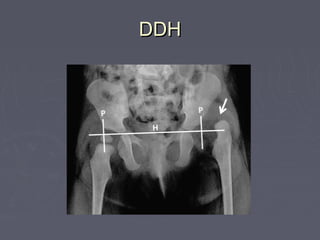

DDHDDH

►Breech presentationBreech presentation

►Ist born femaleIst born female

►Family historyFamily history